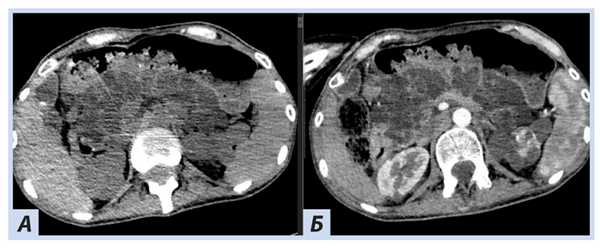

При ультразвуковом исследовании поджелудочной железы эхографическая картина неотчетлива, по данным КТ паренхима поджелудочной железы диффузно изменена за счет множественных тонкостенных кист, вирсунгов проток не прослеживается (рис. 7).

Рис. 7. Пациентка П., 30 лет, с диагнозом «Болезнь Гиппеля−Линдау»: компьютерная томография поджелудочной железы

Примечание. А — нативная фаза: множественные тонкостенные кисты поджелудочной железы; Б — артериальная фаза: кисты визуализируются более отчетливо на фоне контрастированной окружающей ткани железы, но при этом участков патологического накопления поджелудочной железой нет.